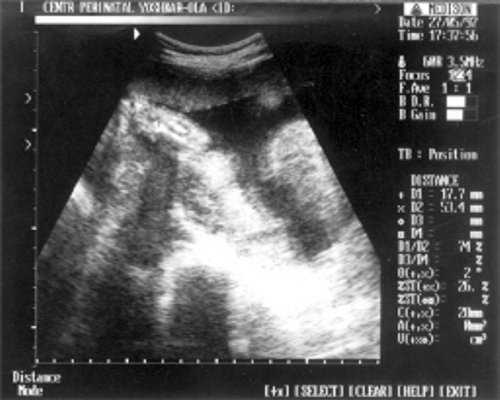

- МРМ (межполушарный размер мозжечка) = 25,6 мм - 23,5-24 нед. (рис. 1)

Рис. 1. УЗИ плода - голова.